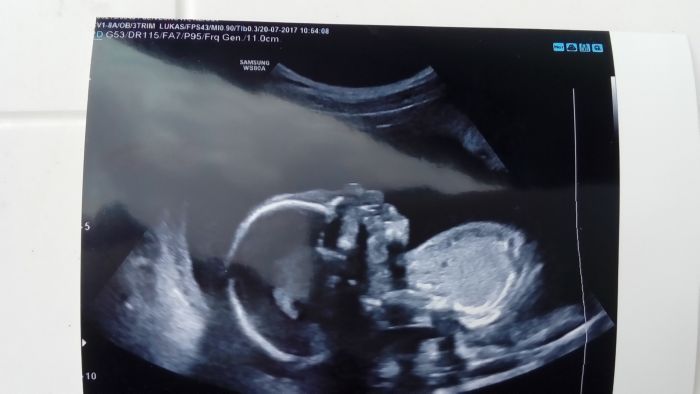

Ahoj holky tak vše je OK. velikost odpovídá tomuto týdnu. A byl tam PINDIK takže pan doktor se ve 12 týdnu měl pravdu :)...dneska jsem to vzala dobře už jsem se s tím totiž vyrovnala takže mi to nevadí hlavně že je vše ok...myslela jsem že mi budou dělat i testy na tu genetiku ale když už jsem ju měla v tom 12tt tak to nahrazuje tyto...jen jsem dostala žádanku na kardio srdíčka aby to lépe prošetřili byla jsem i u prvního. Mám šelest na srdci tak asi kvůli tomu ale říkal že on sám vidí vše v pořádku :) fotku vám pošlu večer. Jinak hrozně byl aktivní takže nešla 3D udělat..takhle aktivní snad ještě nebyl úplně se mě hýbalo břicho.